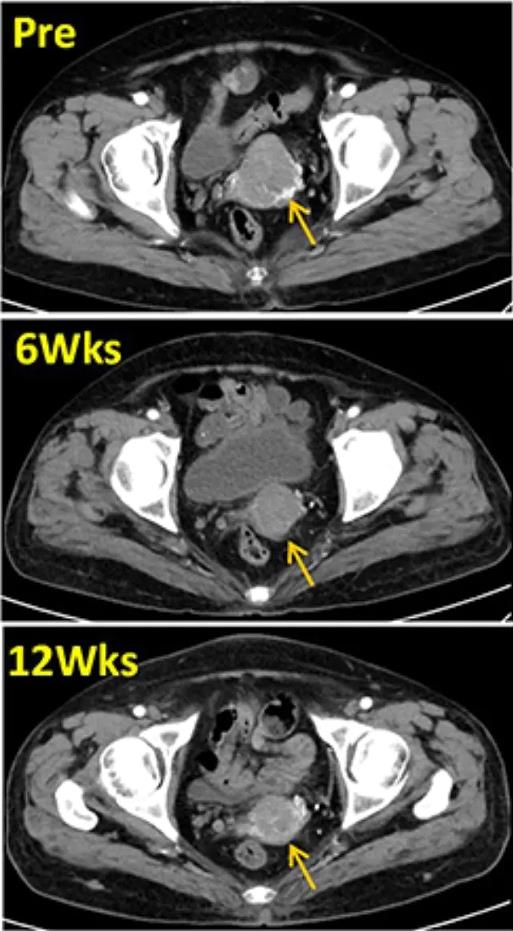

3、增强盆腔CT:患者在回输TIL前、治疗后6周、治疗后12周时,增强盆腔CT扫描目标病灶分别为4.9cm、3.3cm、3.0cm。显然,回输TIL细胞后,患者的肿瘤病灶迅速缩小(详见图1)。

图1 TIL治疗前后,盆腔增强CT对比

▲图源“Dovepress”,版权归原作者所有,如无意中侵犯了知识产权,请联系我们删除